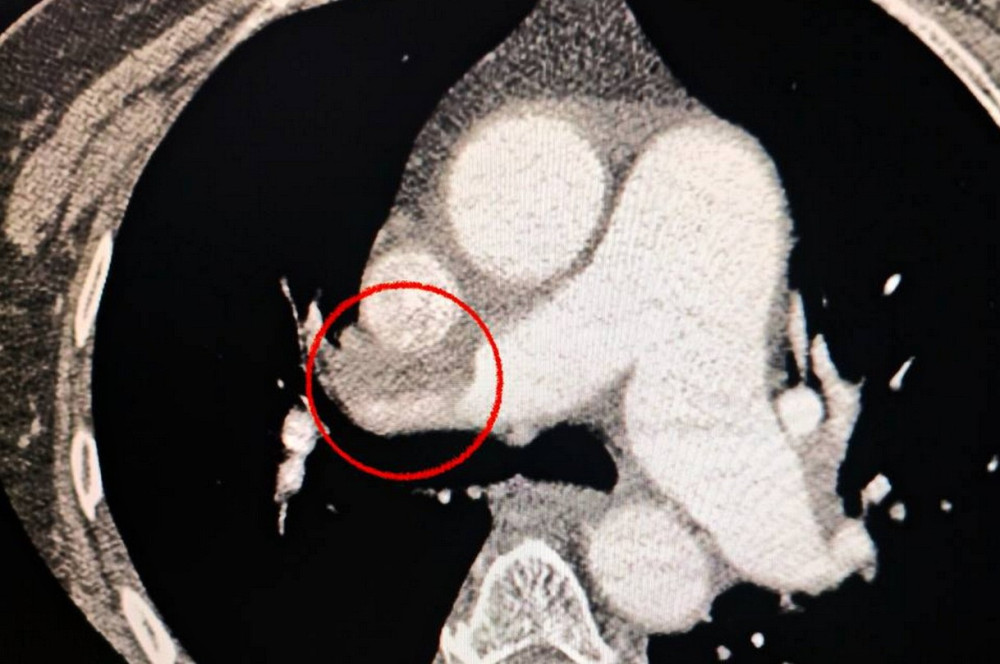

Уникальная хирургическая операция в Одессе

В Одесской больнице успешно проведена уникальная операция по лечению инсульта и тромбоэмболии.

Новые подходы к лечению инсульта: опыт одесских врачей